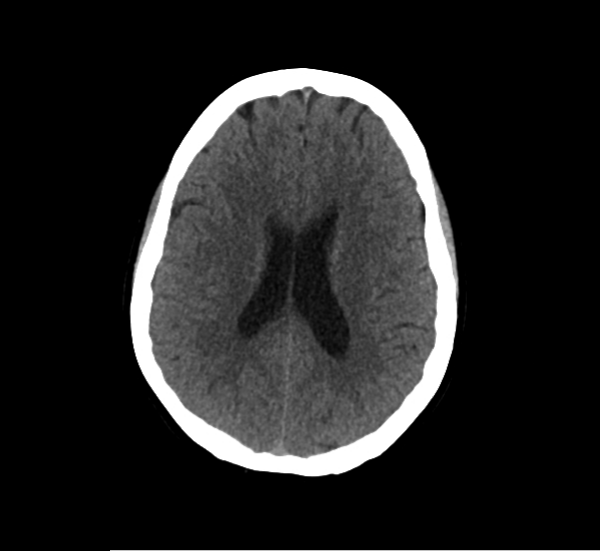

CT Brain Anatomy